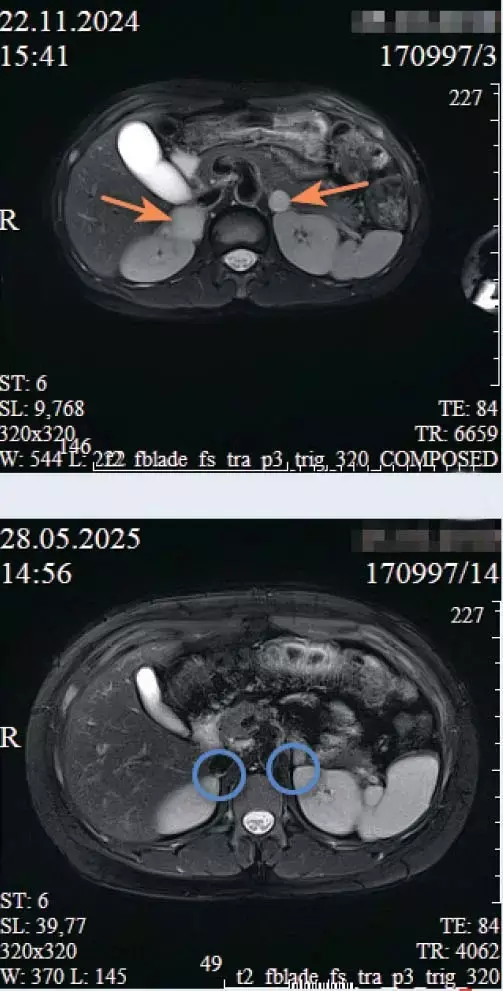

При поступлении сохранялась злокачественная артериальная гипертензия (188/124 мм рт. ст.). КТ и МРТ брюшной полости с контрастированием выявили двусторонние объемные образования надпочечников: справа — солидно-кистозный узел 36×43×55 мм, слева — не менее двух образований до 17 мм. Лабораторно подтвержден гиперкатехоламиновый синдром.

Двусторонняя феохромоцитома: а) до операции; б) после лапароскопической двусторонней туморадреналэктомии.Контрольные УЗИ и МРТ подтвердили отсутствие объемных образований в ложе надпочечников, что свидетельствовало о радикальности операции. Выявленные неспецифические диффузные изменения паренхимы печени и поджелудочной железы трактовались как следствие перенесенной катехоламиновой интоксикации. Киста головки поджелудочной железы оставалась без динамики, что исключило ее опухолевую природу.